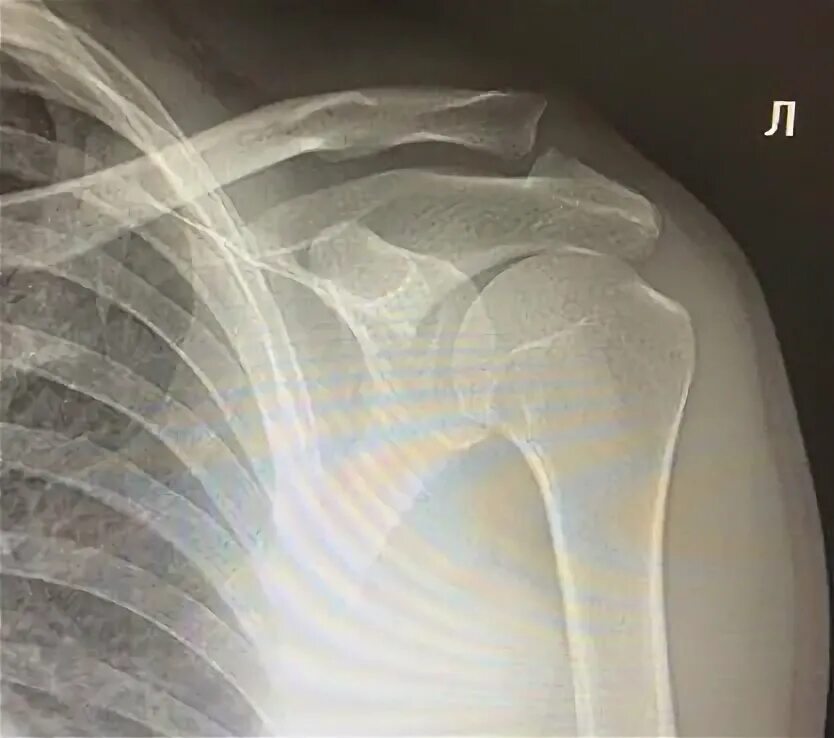

Доа ключично акромиального сочленения